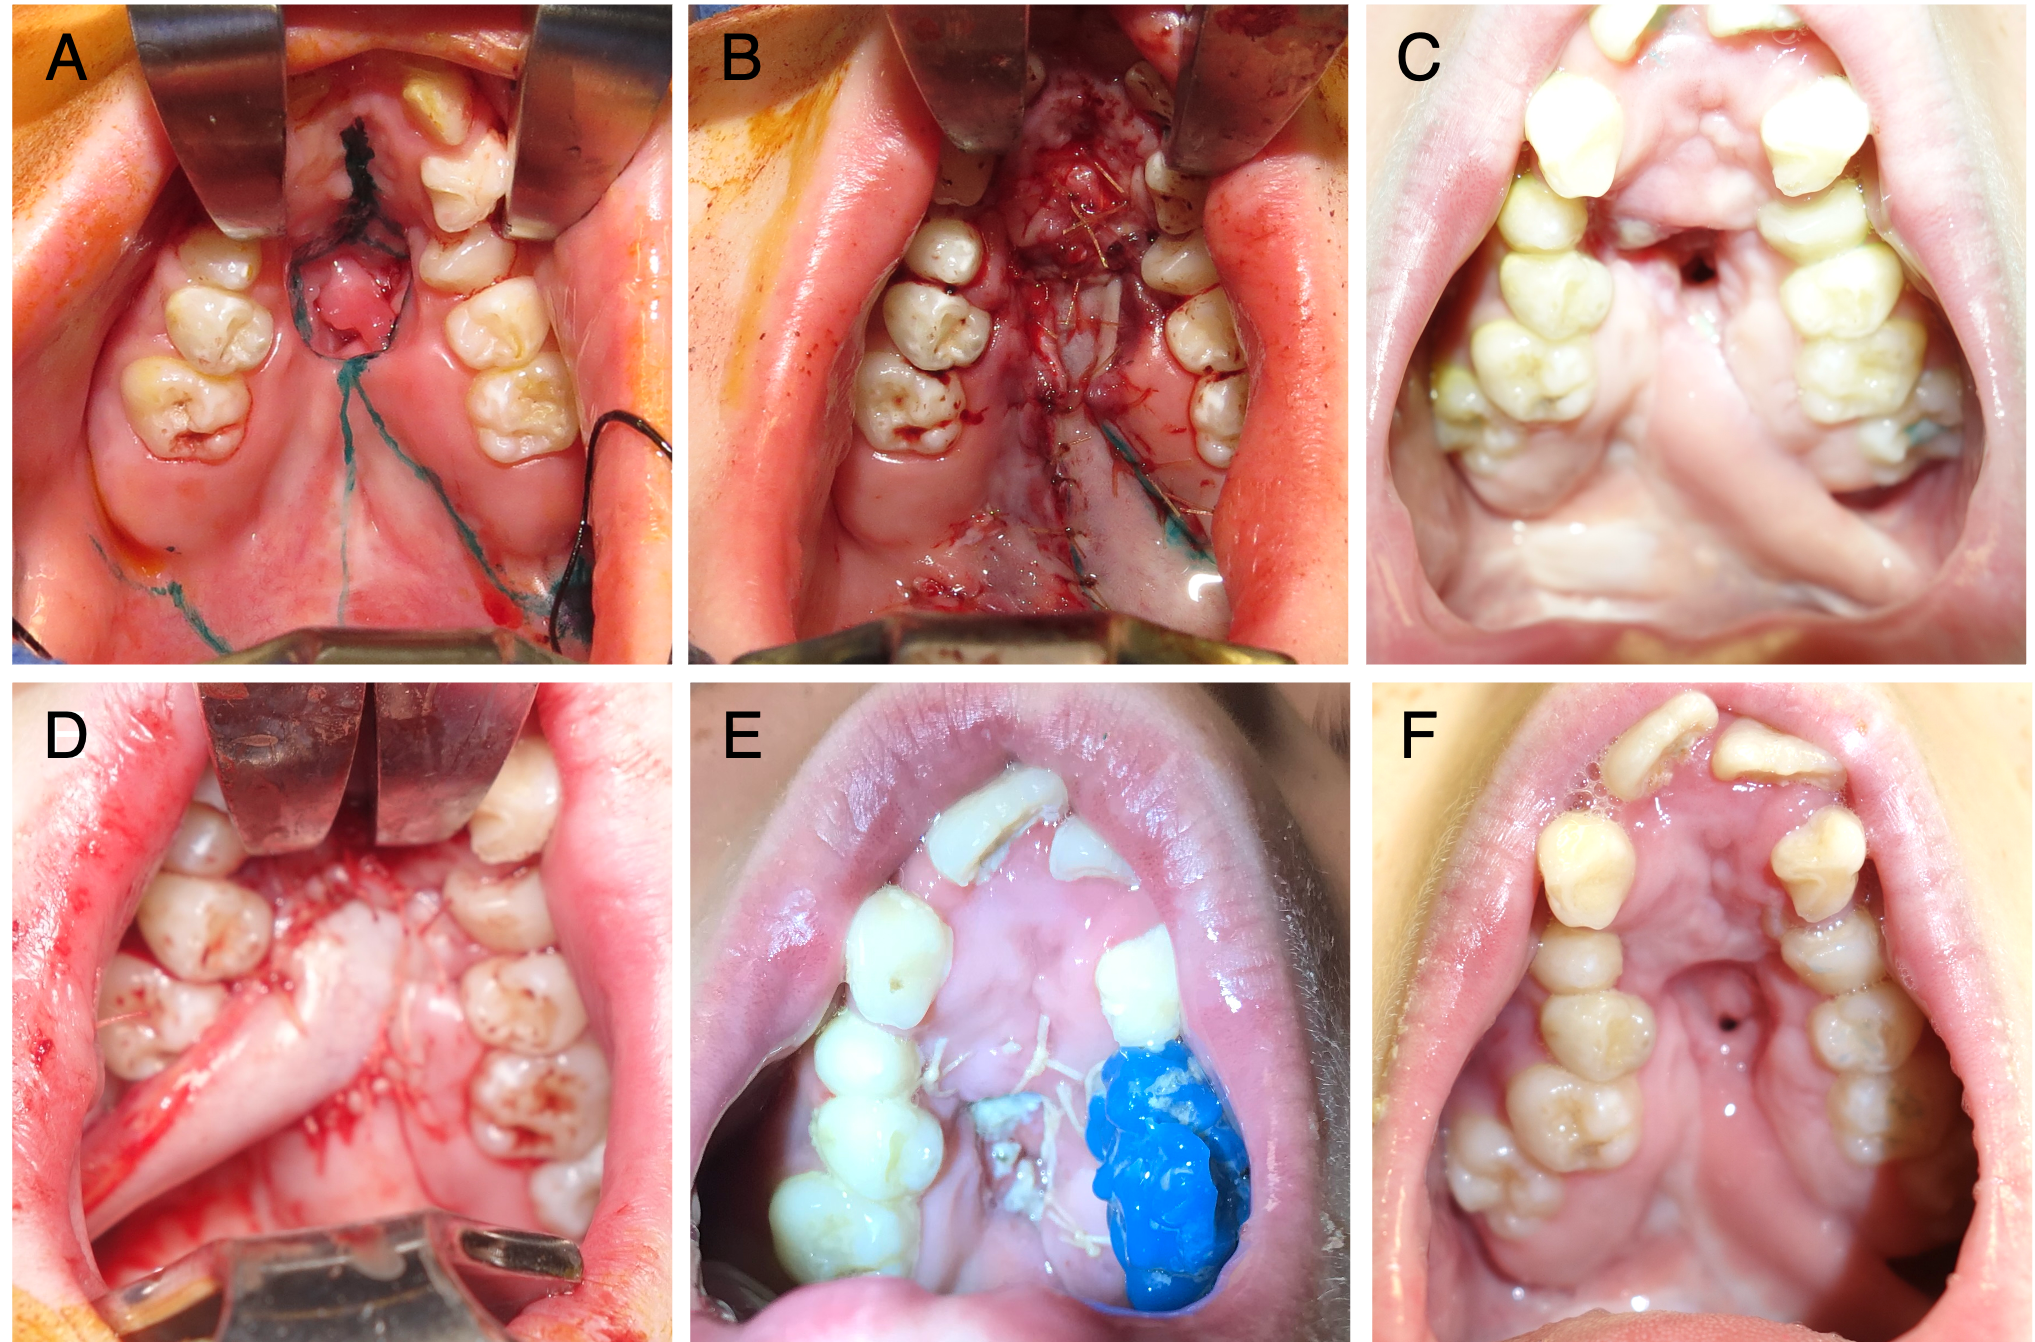

Figure 3. (A) A patient with a history of orofacial digital syndrome and cleft palate repaired elsewhere. The patient had severe maxillary restriction and a large hard palate (Type IV) fistula. Fistula repair was undertaken prior to palatal expansion to avoid an enlarging fistula. (B) The patient underwent a conversion Furlow palatoplasty and a left buccal myomucosal flap (BMMF) for coverage of the posterior and middle 50% of the hard palate. (C) The flap reached the posterior third of the palate, but closure was compromised anteriorly, leading to tip necrosis and recurrence of the fistula, which did not respond to readvancement. (D) Revision surgery with a right BMMF taken across the occlusal plane. (E) A contralateral bite block was placed for flap protection. (F) Healing progressed well until the patient disrupted the flap inset with digital manipulation, resulting in a small, non-functional residual fistula.

The use of posteriorly based BMMFs for primary and secondary palatoplasties has gained popularity in recent years following the publications of Robert Mann.55,63 In Mann’s buccal flap palatoplasty procedure, the velum is lengthened and the levator veli palatini is repositioned by cutting the velum free of the posterior hard palate.55 The resulting nasal and oral lining defect is filled with bilateral BMMFs (one side is used for nasal lining and the other is utilized for oral lining).55 In many cases of fistula repair, the periphery of the fistula may be incised circumferentially to recruit sufficient oral lining to facilitate primary closure of the nasal lining (Figure 4A and B). In these cases, a greater oral defect is created, necessitating a local-regional flap for oral lining; s unilateral BMMF may be sufficient (Figure 4C and D).

Figure 4. (A) A patient with a history of bilateral cleft lip and palate repaired elsewhere and 1 prior fistula repair attempt, presenting with a Type III fistula. (B) Markings for a conversion Furlow palatoplasty and left buccal myomucosal flap (BMMF). (C) Intraoperative view following flap elevation and inset, with the BMMF passed behind the dentition without occlusal impingement. (D) Healed flap, with division and inset planned for a future procedure.

Six patients underwent 7 fistula repairs using the BMMF (Table 1). The cohort consisted of 2 males and 4 females, with repairs performed at a median age of 7.0 years (range, 2.1-18.7 years). The median length of follow-up was 118 months (range, 20-180 months). Two patients had isolated cleft palate, 2 had unilateral cleft lip and palate, and 2 had bilateral cleft lip and palate. The median hospital length of stay (LOS) was 32 hours (range, 30-48 hours). The buccal flap was brought across the occlusal plane in 6 of the 7 flaps. A bite block was used in 2 cases to protect the pedicle from masticatory trauma. The flap was divided and inset in 3 cases, with 2 requiring early inset. Successful fistula closure was achieved in 66.7% (4) of the patients. Two patients experienced flap dehiscence. The first patient was a 2-year-old who had recurrent sinus infections and nasal drainage, as well as reported digital manipulation of the flap. The second patient underwent concurrent Furlow palatoplasty for VPD and Type IV fistula repair with a unilateral BMMF (Figure 3B). The fistula size was decreased, but loss of the distal tip of the BMMF resulted in a 2- to 3-mm fistula recurrence, which was unsuccessfully treated with re-elevation and advancement of the flap (Figure 3C). Severe palatal constriction raised concerns about potential fistula enlargement with palatal expansion, and a third attempt at fistula repair with a contralateral BMMF (Figure 3D) was undertaken with a protective bite block (Figure 3E). Digital manipulation by the patient resulted in flap dehiscence, but secondary healing resulted in no functional fistula after orthodontic treatment (Figure 3F).